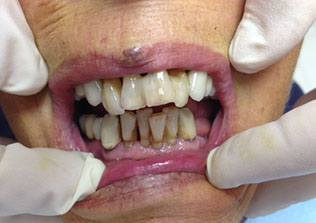

L’implantologia all on 4

è la nuova frontiera della protesi impiantare a carico immediato: consente di eseguire una protesi dentale fissa totale (ovvero che sostituisce tutti i denti di un’arcata, superiore e/o inferiore) con l’inserimento di soli quattro impianti.

Fino a 10 anni fa il paziente che aveva perso tutti i denti era costretto a portare una protesi dentale mobile (ovvero la classica dentiera) ma da oggi, grazie alla tecnica all on four, è possibile donare al paziente un nuovo sorriso, con risultati estetici, funzionali e di confort eccellenti. La protesi all-on-4 è fissa, ovvero ancorata agli impianti, quindi il paziente non la dovrà togliere per l’igiene di routine; sarà come avere di nuovo i propri denti.

L’implantologia all-on-four è stata ideata dal Dr. Malò e prevede l’inserimento strategico di 4  impianti di cui 2 inclinati.